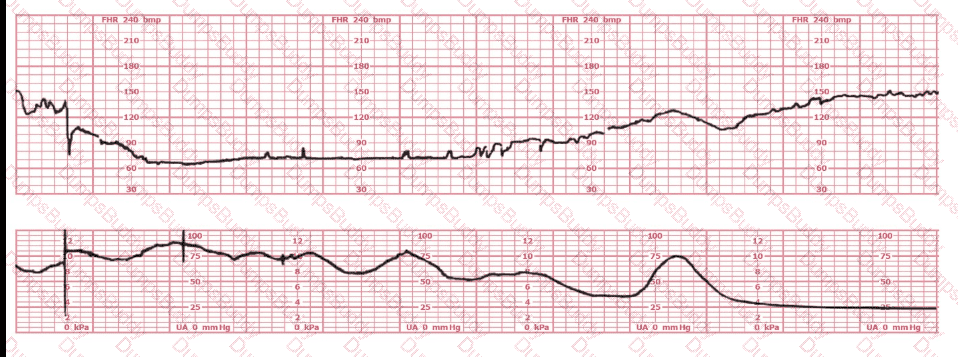

A woman at 38-weeks gestation is admitted to labor and delivery following a fall down the stairs three hours ago. She started feeling contractions in the ambulance. The fetal heart rate tracing shown is on initial evaluation and represents 25 minutes. This tracing is most consistent with a